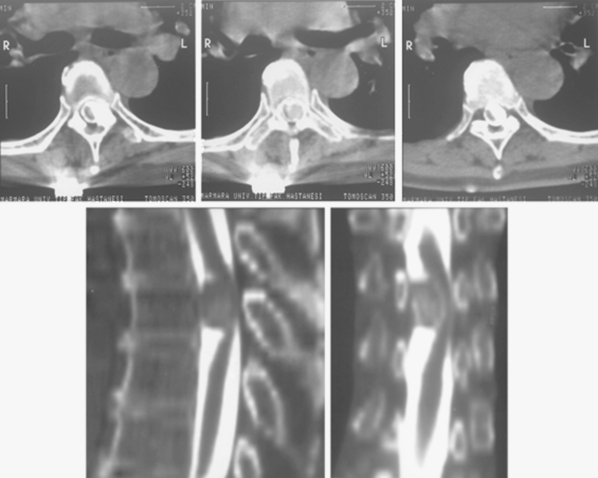

髓内脊髓肿瘤(IMSCTs),如下图所示,是指硬膜内 脊髓肿瘤 的一个亚群,由脊髓内的细胞产生,与相邻结构如神经根或脑膜相对。它们比脑瘤少见得多,据认...

脊髓肿瘤 是在脊髓内或周围发生的非癌性(良性)或癌性(恶性)生长。人们可能会有肌肉无力,失去身体特定部位的感觉,或无法控制肠道和膀胱的功能。磁...